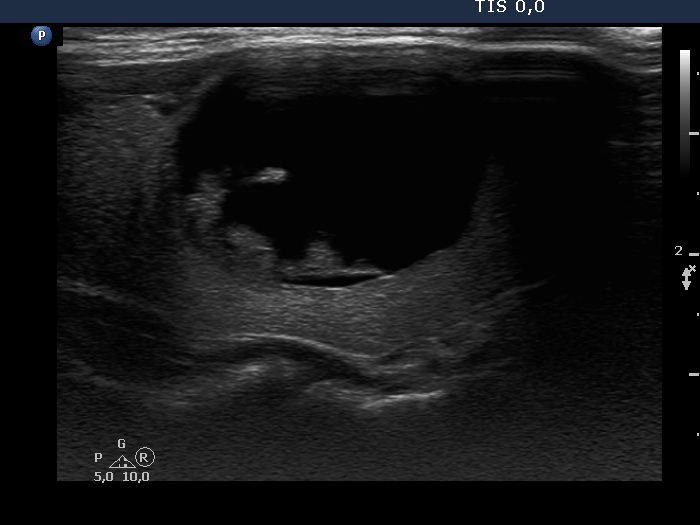

The composition of the nodule - case 753 (ultrasonographic picture 4)

Right lobe, another longitudinal scan.